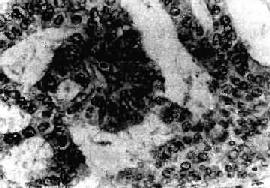

三、子宫肿瘤(一)子宫平滑肌瘤 子宫平滑肌瘤(leiomyoma)是女性生殖器官中最常见的一种良性肿瘤,多见于30~50岁妇女,20岁以下罕见,绝经后肌瘤可逐渐萎缩。其发生可能与过度的雌激素刺激有关。临床上多数患者可无症状,若出现症状,则表现为月经过多及局部肿块等。 【病变】 肉眼观,肌瘤可以生长在子宫任何部位,常位于子宫壁内(肌层内肌瘤)、浆膜下(浆膜下肌瘤)或粘膜下(粘膜下肌瘤)。可单发或多发,常为多个,其数目多少不等,常见为数个、乃至十数个或数十个,称多发性平滑肌瘤。肌瘤的大小可极为悬殊,小的在显微镜下才可检见,大的如成人拳大或更大,甚至可充满整个腹腔。肌瘤多呈球形或融合成不规则形,质较硬,界限明显,但无明显包膜(图13-7)。切面上,瘤组织常呈灰白色,编织状或旋涡状,当肌瘤生长较快或供血不足时,可发生各种继发性改变,如玻璃样变、粘液变、囊性变、水肿及出血、坏死等。

图13-7 子宫平滑肌瘤 多个肌瘤结节,位于肌壁内、粘膜下及浆膜下,境界分明,宫腔受挤压呈裂隙状 镜下,瘤细胞与正常子宫平滑肌细胞相似,但肌瘤细胞核比较密集,常排列成纵横交错的不规则束状或成编织状。核大多呈长杆状、两端钝圆或圆锥形,染色质纤细。肌细胞间有不等量的结缔组织。每10个高倍(400倍)视野核分裂像少于5个者一般为良性。有少数病例瘤细胞核增多、致密,核大活跃,染色质粗,无核分裂像,称细胞性平滑肌瘤(cellular leiomyoma)。子宫平滑肌瘤的恶变率很低,据报道为0.2%~0.5%,多见于年龄较大、生长较快与较大的肌瘤。如果核分裂像每个高倍视野达10个以上或有肌层及血管浸润者应诊断平滑肌肉瘤。 (二)子宫体癌 子宫体癌又称子宫内膜癌(carcinoma of endometrium),较常见,占女性生殖道恶性肿瘤的20%~30%。近年来子宫体癌的发病率有上升趋势。多发生在50岁以上绝经期和绝经期后妇女。病因未明,一般认为与雌激素长期持续作用有关。主要临床表现为不规则阴道流血。 【病变】 肉眼观,分弥漫型及局限型两种。弥漫型的子宫内膜呈弥漫增厚,不规则形、息肉或菜花状,质脆,常见出血、坏死或溃疡形成。癌组织浸润肌层,深浅不一(图13-8)。局限型多位于宫底或宫角,后壁多于前壁,常呈息肉状伴肌层浸润。